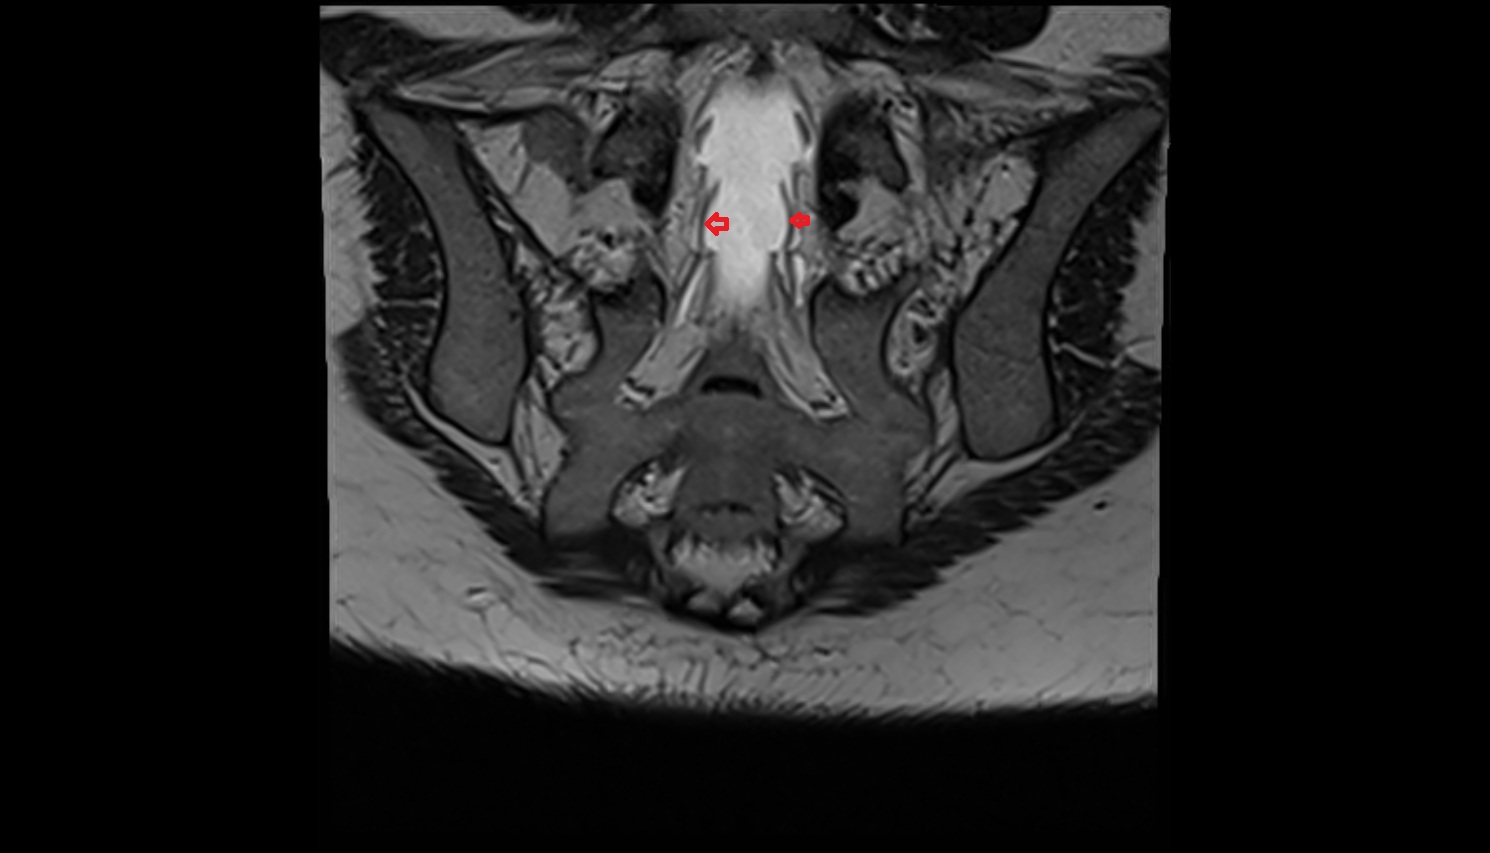

- Peripheral zone of prostate

- Anterior Fibromuscular Stroma of prostate

- Central zone of prostate

- Transitional zone of prostate